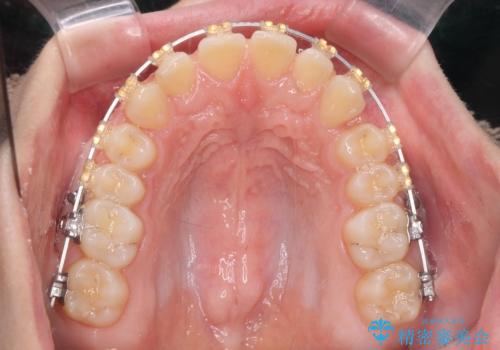

- 矯正装置

- ワイヤー矯正

ワイヤーを用いたマルチブラケット矯正を行うことで深い噛み合わせを改善し、前歯の隙間もなくし審美的な歯列へと治療をおこなっていきます。

深い噛み合わせの改善は前歯の圧下が必要なため、治療期間が長期化することが多いです。